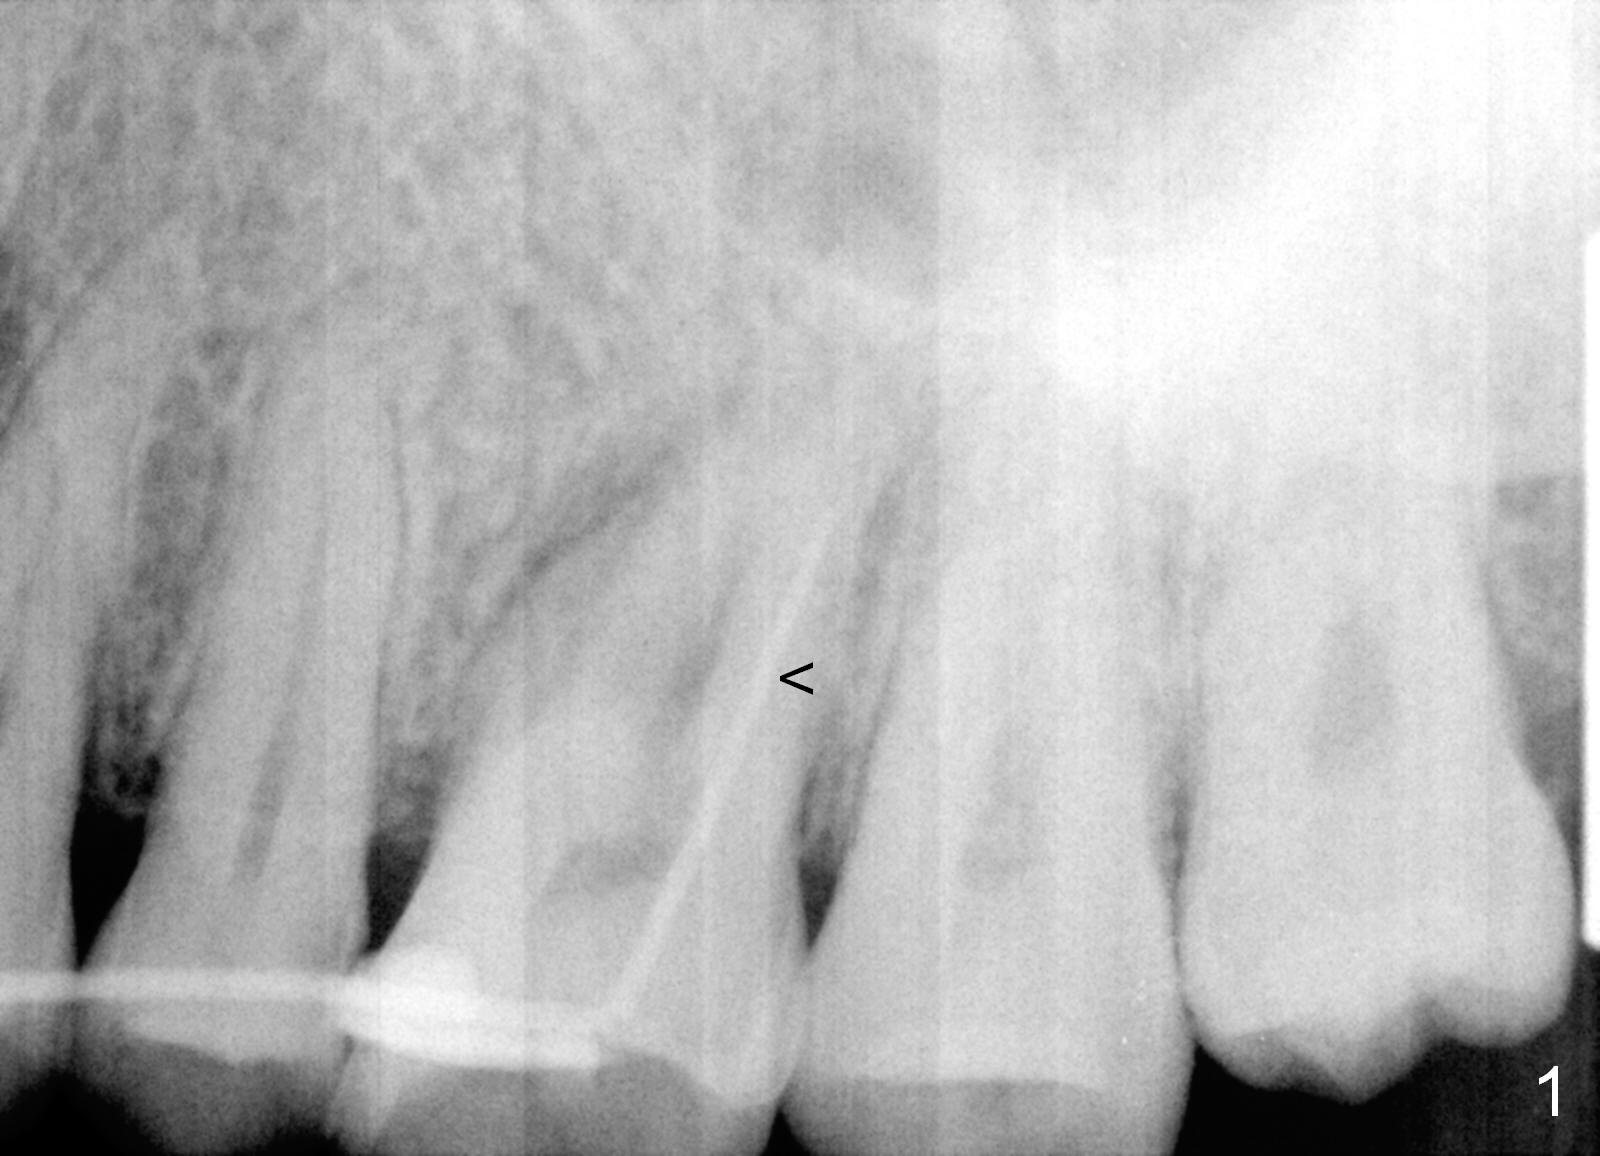

A 46-year-old woman has apical periodontitis with distal crack line at #14. There are 2 fistulae (buccal and palatal). A gutta percha is inserted into the buccal one (Fig.1 <). After extraction and Xylocaine gauze application in the socket, use 1.6 mm pilot drill in the septum for 7 mm, followed by Magic split and expanders for sinus lift. Place a relatively small implant (IBS, 4.5x13 or 5x11 mm, Fig.2) in the septum or a large one (6x13 mm or 6 mm 1-piece one, Fig.3) to obliterate the whole socket.